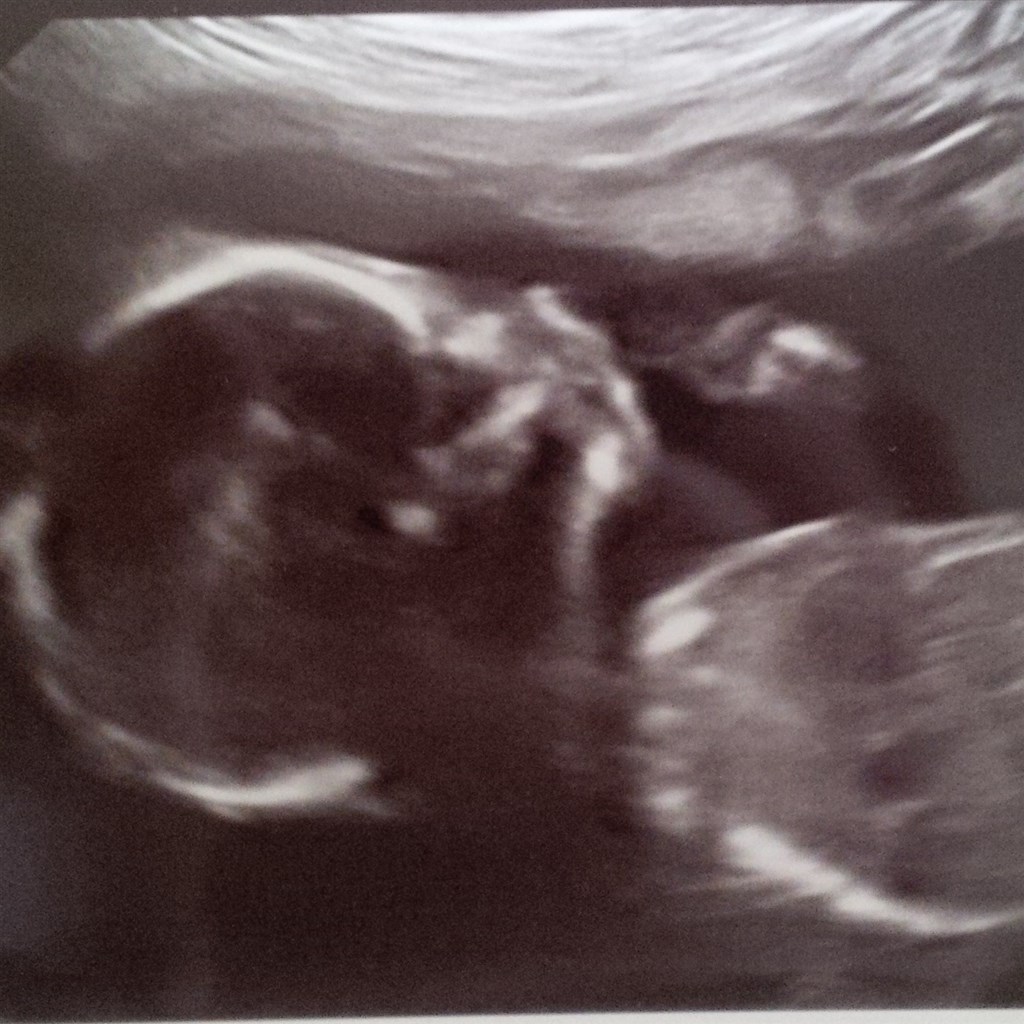

Vi var til misdannelsesscanning i går. Det gik simpelthen så fint. Det eneste var lige, at den lille skumfidus lå og sov og bestemt ikke syntes, at hun havde lyst til at bevæge sig efter jordemoderens ønske.

Det betød så, at vi fik ekstra tid til scanningen, så det var jo meget dejligt.

Status er nu ca. 20 cm lang og 285 gram. Og så er hun bare så fin!